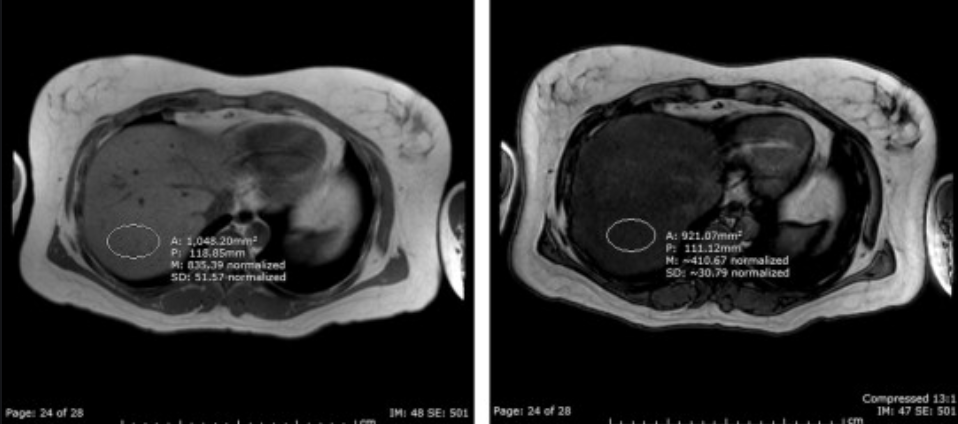

MRI of the liver:

Ix: How MR in/out works.

Ix: when water & fat protons are in the same MR voxel the fat/water signals are summed in in-phase, subtracted in out-of-phase.